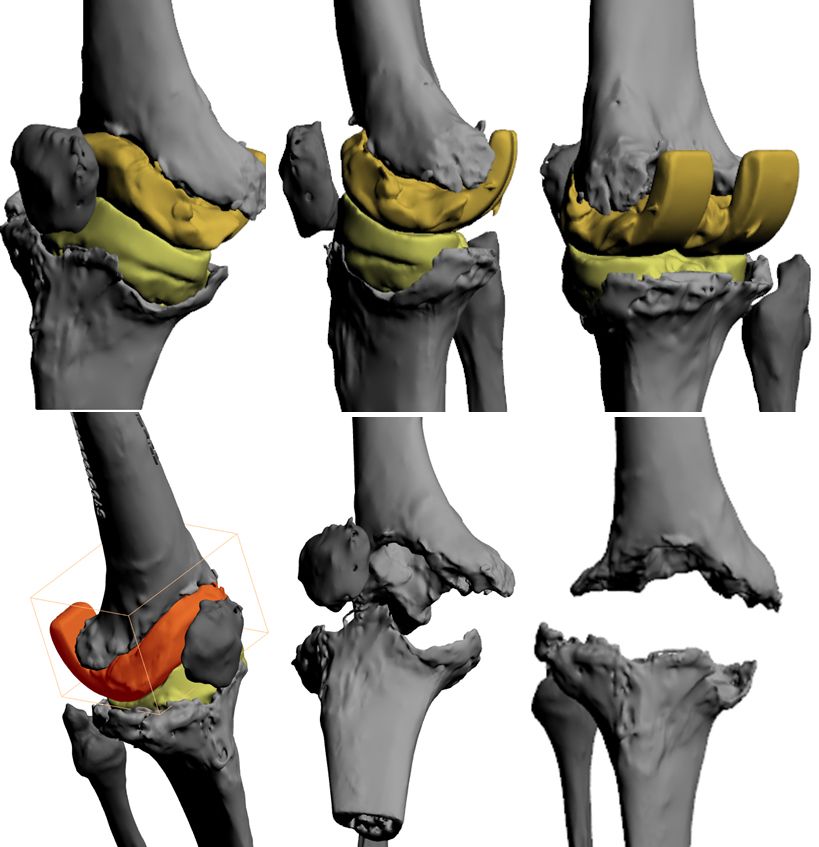

The first step is the image processing that provides a 3D virtual model (HA3D™ reconstruction) of the knee, based on high resolution CT scans. It focuses on the reconstruction of bone structures outside the spacer and/or implants. The next step is the printing of the HA3D™ mathematical model into the correlated interactive 3D PDF allowing navigation (Fig. 5).

With the HA3D™ model, a complete case report with all relevant measurements is provided. After the validation of the printed project, the model is produced with additive manufacturing technology, in particular FDM (Fused Deposition Modeling) technology. PLA (Polylactic Acid) material is the most commonly used for 3D models (Fig. 6-8).

A few days before surgery, the surgeon and nurse can "implant" the real prosthesis and perform the upcoming procedure (fig. 6-8) using real instrumentation on the newly produced 3D model to determine the size of the components (fig. 9) and the need for wedges or cones, if necessary, to restore the correct position and rotation of the joint axis.

The preoperative use of the 3D model (Fig. 17) allows the surgeon to plan the operation, to study anatomy and bone loss and to identify the best option for reconstruction, with the possibility to switch from one solution to another (e.g. rods or cones, offset..., Figs. 18-20) and to choose the most appropriate one in order to save time and reduce unnecessary manoeuvres during the operation.

Case 3 further demonstrates the advantages of 3D models for a 77 years old woman after two stage revision for septic loosening of a cemented primary implant 12 years ago. After reinfection and several AB spacers, bone stock on both femoral and tibial sides was compromised (see also fig. 1). Re-Revision surgery was planned with RHK using cones for both the tibia and femur (Figs 18 and 20).